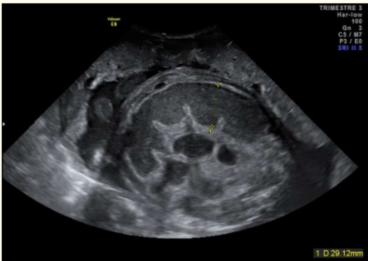

怀孕8个多月的“准妈妈”正欣喜期盼新生命的降生不料,一场生命危机正悄然逼近腹中的孩子生死时刻西南医科大学附属医院产科、小儿外科、麻醉科、新生儿科等多学科团队合力展开了对这个小生命的救治……胎儿告急,紧急剖宫一个多月前,怀孕34周+6天的孕妇...